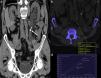

Renal colic is a common reason for presentation to emergency departments, and imaging has become fundamental for the diagnosis and clinical management of this condition. Ultrasonography and particularly noncontrast computed tomography have good diagnostic performance in diagnosing renal colic. Radiologic management will depend on the tools available at the center and on the characteristics of the patient. It is essential to use computed tomography techniques that minimize radiation and to use alternatives like ultrasonography in pregnant patients and children. In this article, we review the epidemiology, clinical and radiologic presentations, and clinical management of ureteral lithiasis.